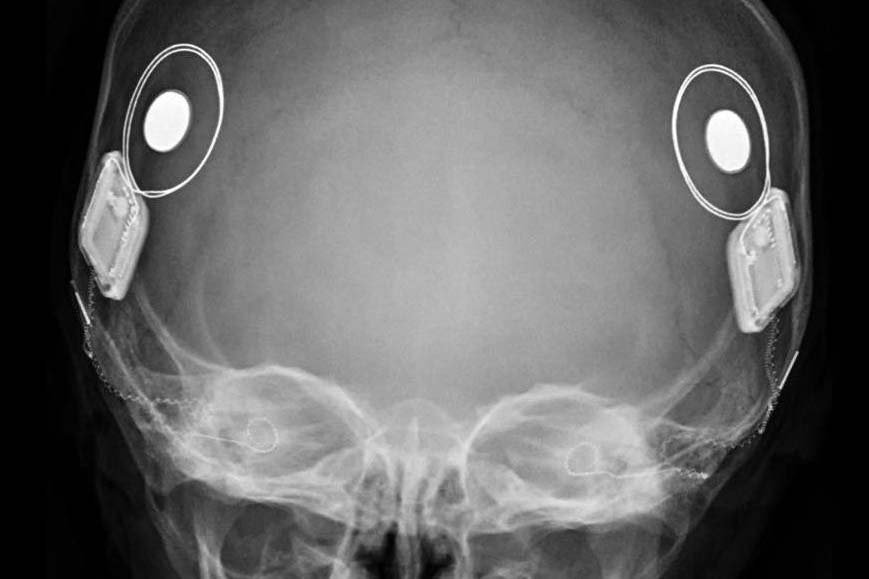

Diferente do aparelho auditivo tradicional, o implante coclear não apenas amplifica o som. Ele estimula diretamente o nervo auditivo por meio de um dispositivo eletrônico.

O sistema é composto por:

- Parte interna implantada cirurgicamente

- Parte externa com processador de som